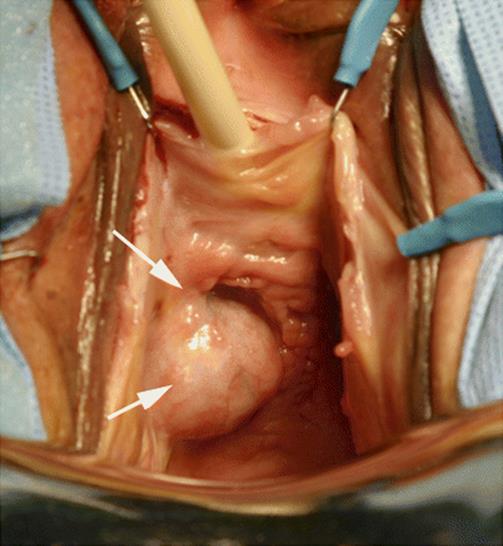

Fig. 8.45

On examination, a large mass is displacing the urethra inferiorly. The mass extends below the inferior ramus of the pubic bone toward the retropubic space. The rest of the anterior and posterior vaginal wall was normal. The arrows point toward the extension of the tumor inferior to the pubic bone

Fig. 8.46

An inverted U flap of the anterior vaginal wall was created over the lesion. The line outlines the incision of the anterior vaginal wall